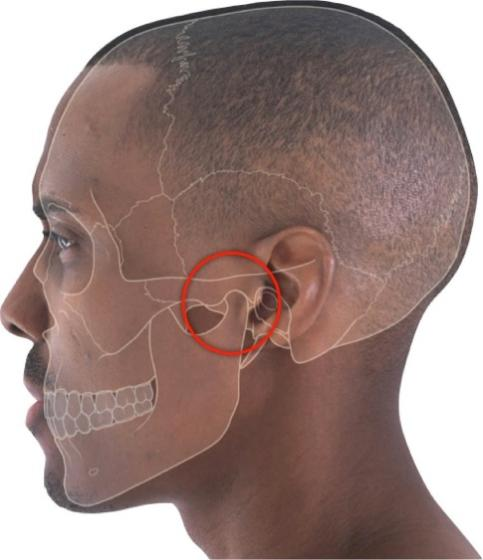

3)颞颌关节:咀嚼食物时疼痛、张口受限,颞颌关节紊乱?抑或风湿病作祟!

颞颌关节紊乱综合征,是口腔科常见疾病之一,临床表现主要包括关节及周围肌肉疼痛、关节绞索、摩擦/破碎音和张口受限等,可对患者的生活质量造成严重影响。

罗医生本人也有左侧颞颌关节骨关节炎,经历过早期的疼痛感后,现在就是长久不愈的咬合时的破碎音……(罗医生已排查过RA)!

临床上,RA合并颞颌关节炎的患者时有遇到,需引起大家足够重视!